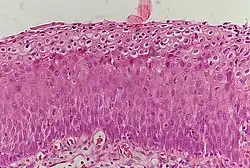

Normal cervical epithelium

Historically, abnormal changes of cervical epithelial cells were described as mild, moderate, or severe epithelial dysplasia. In 1988 the National Cancer Institute developed "The Bethesda System for Reporting Cervical/Vaginal Cytologic Diagnoses".[12] This system provides a uniform way to describe abnormal epithelial cells and determine specimen quality, thus providing clear guidance for clinical management. These abnormalities were classified as squamous or glandular and then further classified by the stage of dysplasia: atypical cells, mild, moderate, severe, and carcinoma.[13]

CIN is classified in grades:[14]

Histology Grade Corresponding Cytology Description Image

CIN 1 (Grade I) Low-grade squamous intraepithelial lesion (LSIL)

• Mild epithelial dysplasia

• Confined to the basal 1/3 of the epithelium

• Typically corresponds to infection with HPV

• High rate of regression back to normal cells

• Usually managed expectantly